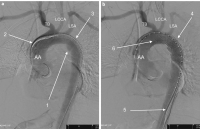

Abbildung 2: 2a: Subtraktionsangiographie vor Absetzen des Stentgrafts: AA – Aorta ascendens; TB – Tr. brachiocephalicus; LCCA – A. carotis communis sinistra; LSA – A. subclavia sinistra; 1 – Pseudoaneurysma; 2 – Spitze des Stentgraftapplikators; 3 – noch nicht expandierter Stent; 2b: Subtraktionsangiographie nach abgesetztem Stentgraft: 4 – freigesetzter Stent, das Pseudoaneurysma ist von der Perfusion exkludiert; 5 – zurückgezogene Spitze des Stentgraftapplikators; 6 – proximales Stentende unmittelbar nach Abgang der LCCA